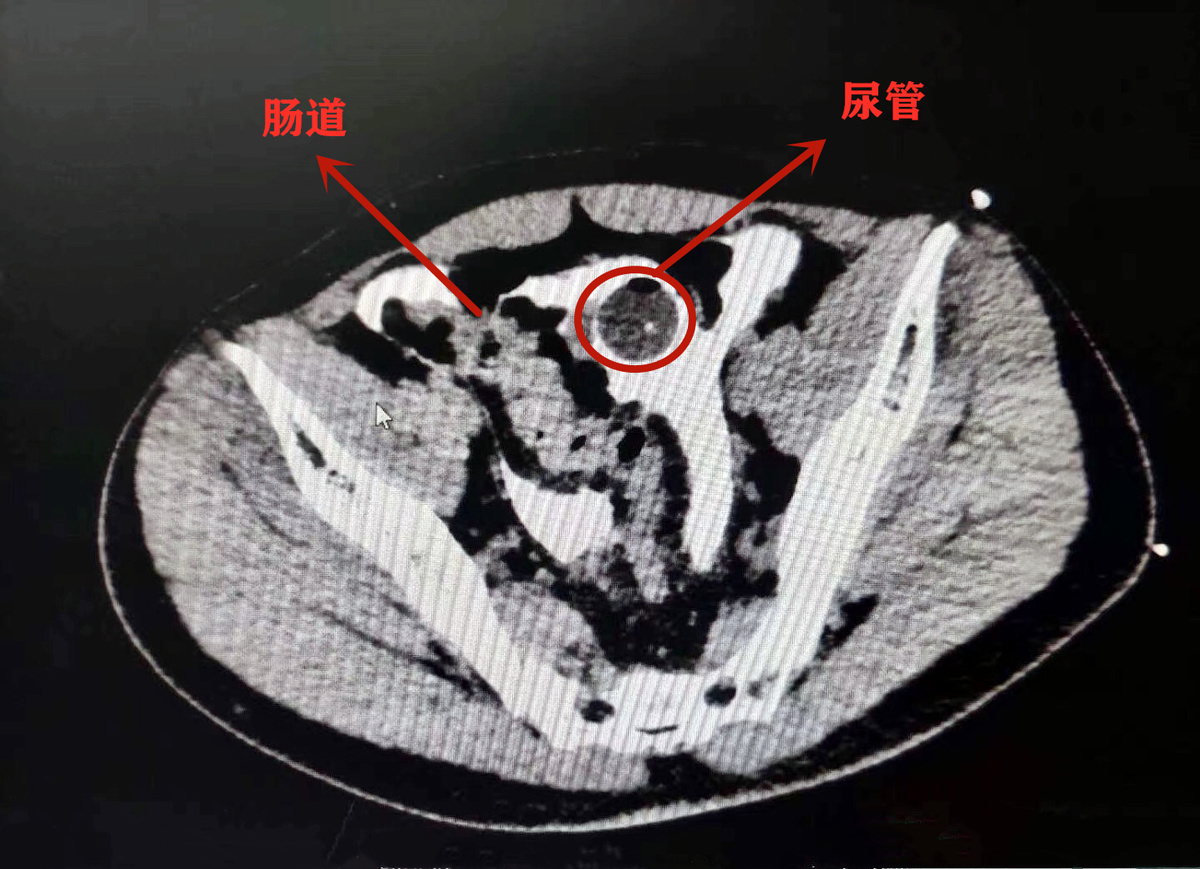

在病床上的小李说起这两天的经历,也是有些哭笑不得。上周六晚上,和朋友相约聚会吃冷淡杯、喝啤酒,期间没上过一次厕所。聚会结束后,站起身的小李脚下一滑摔了一跤,刚好肚子撞在了桌角上。这一撞,让他感觉疼痛难耐,随即被送到了就近的医院。医生先是给他安装了尿管紧急处置,经过进一步检查发现其腹腔内已经有尿液,说明是膀胱发生了破裂。

辗转几家医院,小李在星期天晚上被送到了成都市第三人民医院。该院泌尿外科副主任医师袁仁斌博士说,小李膀胱有一个4*3cm的破洞,尿管也顺着洞“跑”到了腹腔内。因为尿液在腹腔内蓄积了很长时间,已经引发了比较严重的腹膜感染,“如果再不及时手术,可能生命都会受到威胁。”